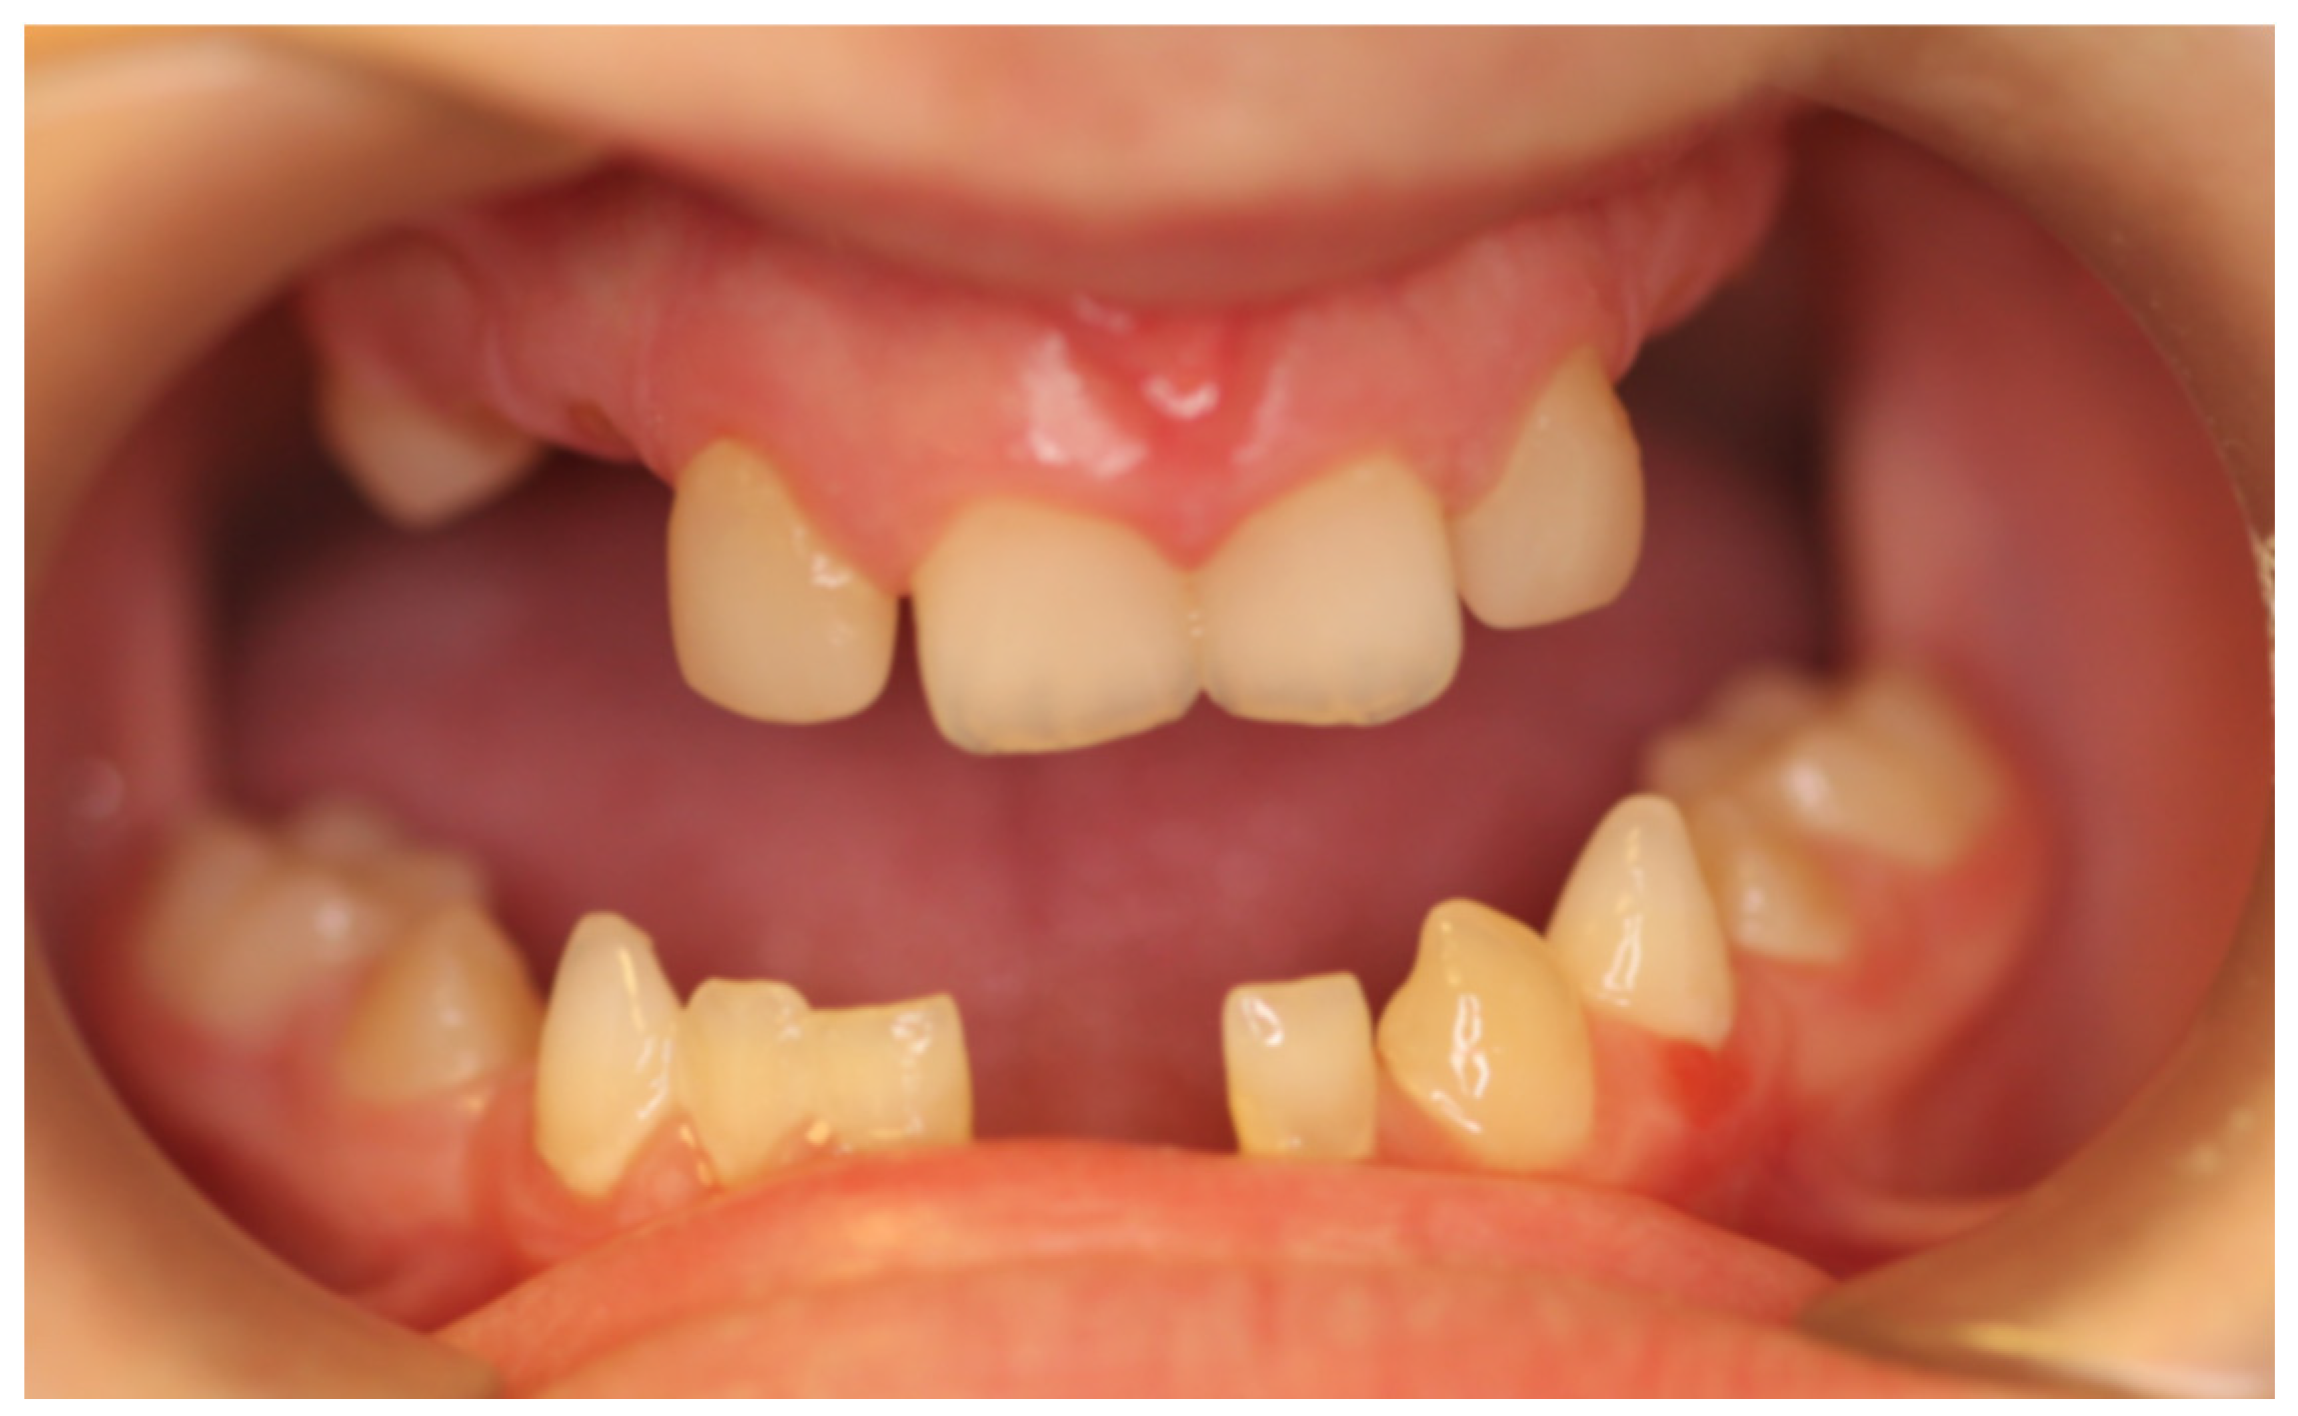

At the initial visit, the permanent teeth present were 15, 34, 33, and 44. The primary teeth present were 75, 72, 81, 82, and 85. Several dental anomalies were observed: The mandibular primary canines (73 and 83) were conical in shape, the maxillary right lateral incisor (12) was peg-shaped, and microdontia was noted in the maxillary central and lateral incisors (11, 21, and 22). Erosive wear was also evident on the maxillary primary molars and canines (54, 53, 63, and 64), suggesting the structural weakening of enamel (Figure 1, Figure 2 and Figure 3).

The child exhibited a narrow maxillary arch along with skeletal class III, resulting in a complete lack of occlusal contact, along with a reduction in both overjet and overbite by approximately 2 mm. A midline assessment was not feasible due to the extent of dental anomalies. Reduced alveolar bone volume was observed to be associated with the underdevelopment of the alveolar ridge. The clinical findings were corroborated by a recent dental panoramic tomogram (DPT) provided by the referring dentist. Radiographic analysis confirmed the agenesis of nineteen permanent teeth, as well as the presence of an impacted mandibular right second premolar (tooth 45) (Figure 4).

Figure 1. Intra-oral photograph, frontal view.